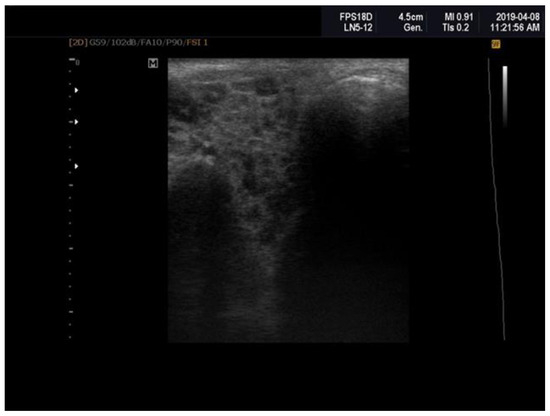

4.3. Salivary Gland Ultrasonography (SGUS)